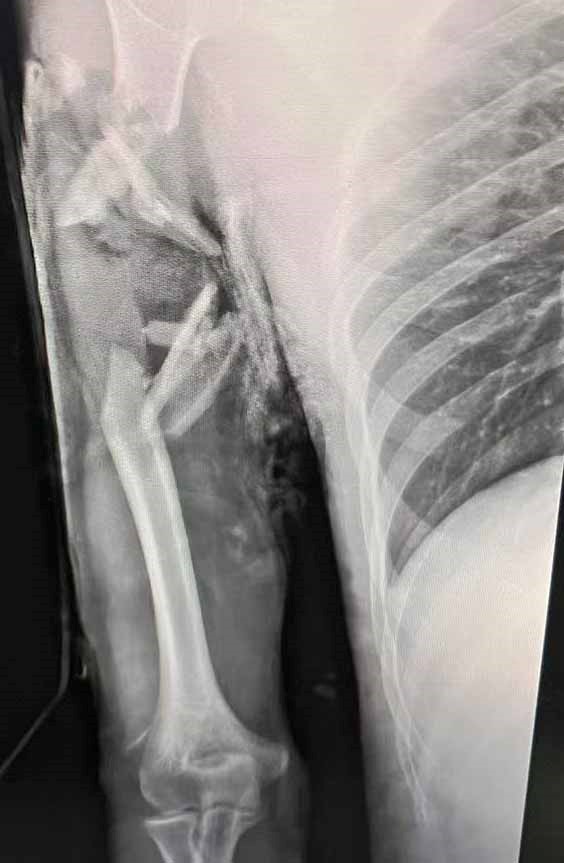

近日,14岁的小霍不慎因交通意外,导致右上臂中上段离断,骨骼、肌肉、神经、血管外露,为了寻求更好的治疗,紧急被120救护车送至我院郑州院区抢救治疗。我院郑州院区手外显微骨三科周明武主任、显微创伤骨科牛洪华主诊医师对伤者进行紧急评估后,立刻申请启动绿色通道,安排手术团队迅速做好各项术前准备。

断臂再植术需要将骨骼固定,肌肉、神经、血管等受损组织进行精确的吻合重建,往往需要经历多次手术,任何一个环节出现问题都会导致手术失败,是一项难度较大、技术要求较高的手术。术中彻底切除无血运以及血运不佳的肌肉,可以避免术后严重的坏死感染;早期通血可以增加患肢的成活率和促进术后功能恢复,尽力缩短组织缺血时间;术中将外露肱骨碎块去除,将肱骨短缩,确保血管、神经吻合时没有张力,有利于血管神经的创面覆盖以及术后神经功能恢复,否则极有可能导致血管栓塞或破裂;再植术毕根据经验彻底切开前臂筋膜,防止骨筋膜室综合征的发生;再植术中始终关注病患者各项指标变化,确保手术安全进行。